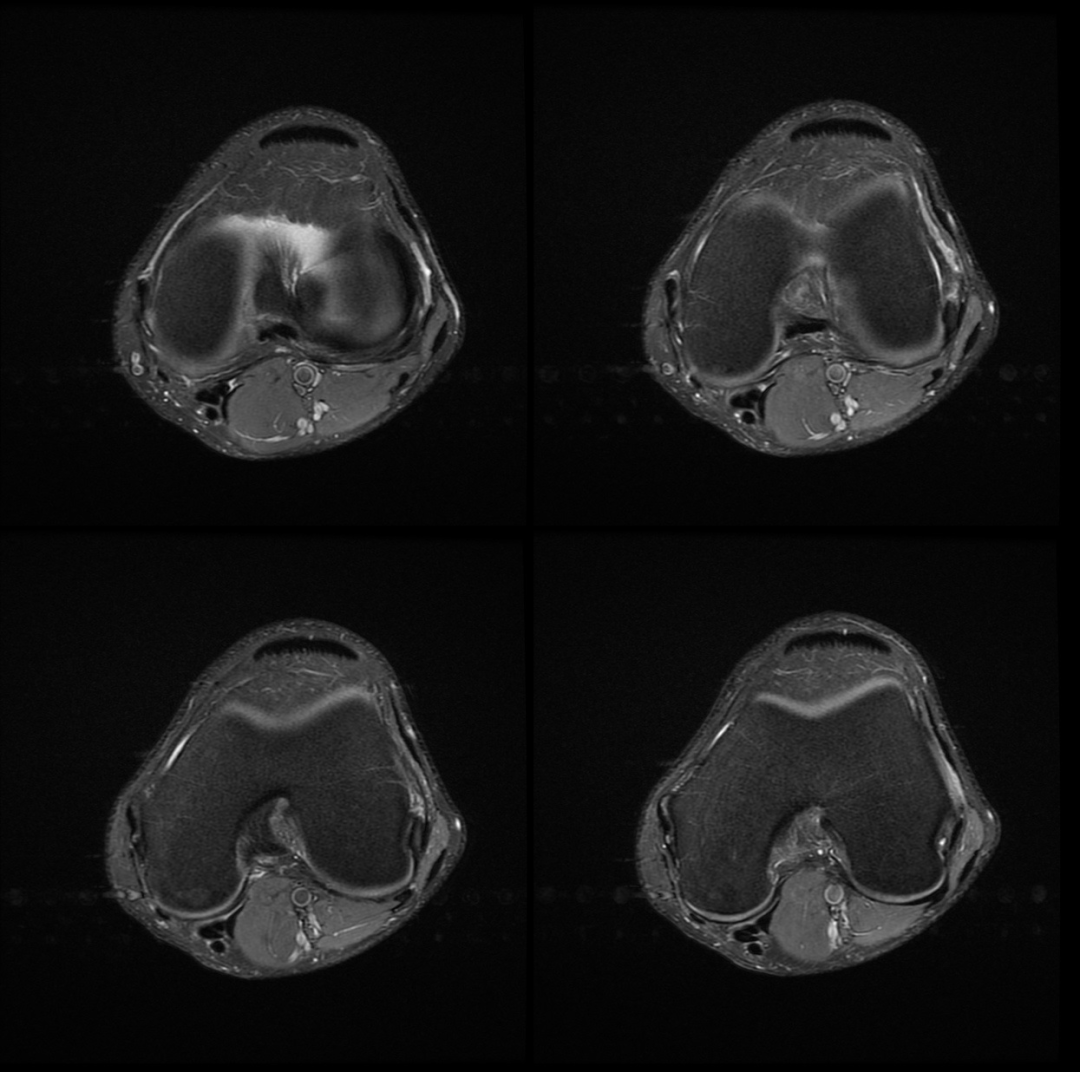

主诉:右膝关节外侧反复疼痛不适半年余,近一个星期疼痛加重。现病史:患者右膝关节外侧间歇性疼痛不适半年余,近一个星期疼痛加重,屈膝时明显,门诊行膝关节 X 线片检查,未见明显异常。患者否认手术史/外伤史。为进一步明确情况,我们建议患者行膝关节磁共振检查;图像如下:T1

T2 压脂

冠状位

轴位

大家是否发现什么异常?该患者是膝外侧疼痛不适的症状,我们重点观察了外侧半月板及外侧副韧带,但是我们发现是正常的;

但是我们发现有一个地方信号不对;

大家发现了没有?那这是什么呢?

那么我们刚刚看到信号增高的就是髂胫束,排除了半月板和外侧副韧带的问题,那么膝关节外侧疼痛是不是这个原因导致的呢?

1 T2WI PD 序列上可以显示靠近股骨外侧髁与髂胫束之间的信号增高,边界不清,外侧滑膜增厚;

2 髂胫束靠近股骨外侧髁水平出现增厚改变,部分严重患者可以出现连续性中断;3 髂胫束表面或深部信号明显增高;4 可伴股骨外侧髁反应性骨髓水肿